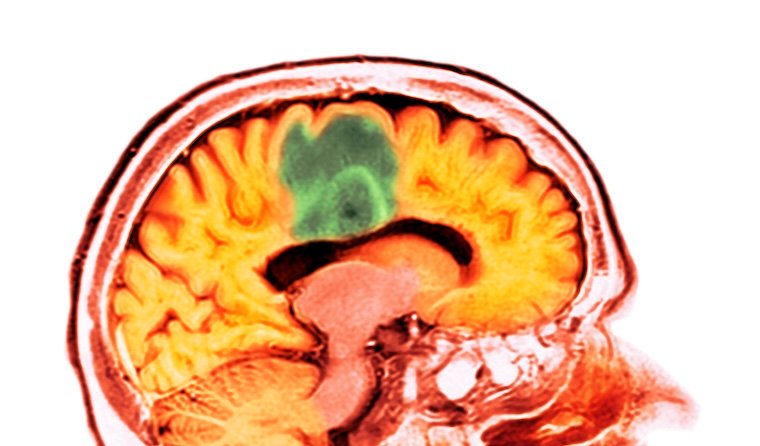

Colorized brain scan

This colorized computed tomography (CT) scan shows a glioblastoma tumor. Glioblastoma is the most deadly form of brain cancer.